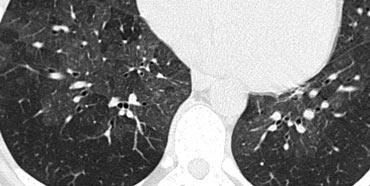

Cystic lung disease

Nang phổi được định nghĩa là các vùng thấu quang với độ dày thành dưới 4mm.

Các bệnh phổi dạng nang được liệt kê trong bảng ở bên trái.

Bên trái là một trường hợp có nhiều nang phân bố đều khắp phổi (trái ngược với LCH).

Lưu ý tình trạng tràn khí màng phổi.

Bệnh nhân không có tiền sử hút thuốc và là nữ giới 40 tuổi.

Sự kết hợp các dấu hiệu này điển hình cho Bệnh U Cơ Bạch Huyết (LAM).

Bệnh u cơ bạch huyết là một bệnh hiếm gặp đặc trưng bởi sự tăng sinh tiến triển của các tế bào hình thoi, giống với cơ trơn.

Sự tăng sinh của các tế bào này dọc theo các tiểu phế quản dẫn đến hiện tượng bẫy khí và hình thành các nang phổi thành mỏng.

Vỡ các nang này có thể gây ra tràn khí màng phổi.

Các biểu hiện khác của LAM bao gồm bệnh hạch và tràn dịch màng phổi.

U cơ mạch bạch huyết chỉ xảy ra ở phụ nữ, thường trong độ tuổi sinh đẻ, từ 17 đến 50 tuổi.

Các biến đổi lâm sàng, X-quang và bệnh lý phổi tương tự được thấy ở khoảng 1% bệnh nhân mắc bệnh xơ cứng củ.

Hầu hết bệnh nhân tử vong trong vòng 10 năm kể từ khi khởi phát triệu chứng.